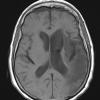

Infarct, Tract Degeneration, illustrative case (2)